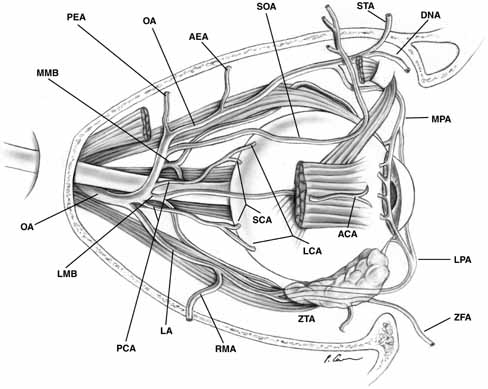

in which the ophthalmic artery gives origin to its branch arteries, the

most frequent pattern is shown in Figure 23.  Fig. 23 Most common branching pattern of the ophthalmic artery in the orbit. (AEA, anterior ethmoidal artery; ANA, anterior ciliary artery; DNA, dorsal nasal artery; LA, lacrimal artery; LCA, long ciliary artery; LMB, lateral muscular branch; LPA, lateral palpebral artery; MMB, medial muscular branch; MPA, medial palpebral artery; OA, ophthalmic artery; PCA, posterior ciliary arteries; PEA, posterior ethmoida1 artery; RMA, recurrent middle meningeal artery; SCA, short ciliary artery; SOA, supraorbital artery; STA, supratrochlear artery; ZFA, zygomaticofacial artery; ZTA, zygomaticotemporal artery) Fig. 23 Most common branching pattern of the ophthalmic artery in the orbit. (AEA, anterior ethmoidal artery; ANA, anterior ciliary artery; DNA, dorsal nasal artery; LA, lacrimal artery; LCA, long ciliary artery; LMB, lateral muscular branch; LPA, lateral palpebral artery; MMB, medial muscular branch; MPA, medial palpebral artery; OA, ophthalmic artery; PCA, posterior ciliary arteries; PEA, posterior ethmoida1 artery; RMA, recurrent middle meningeal artery; SCA, short ciliary artery; SOA, supraorbital artery; STA, supratrochlear artery; ZFA, zygomaticofacial artery; ZTA, zygomaticotemporal artery)

|